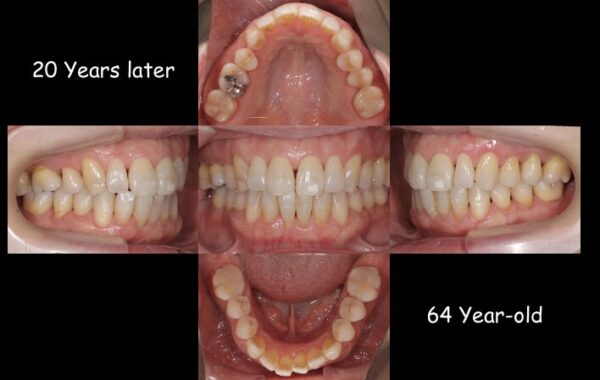

そして、治療終了後20年の状態です。

患者さまは還暦を迎えられましたが、お口の中は非常に健康で若々しい状態を保っておられます。

20年もの長い間、ほぼ歯の治療を行わず済んだのは、第一にこの患者さまがしっかりとお手入れとメンテナンスを欠かさず、努力された事に他なりません。

それに加えて、この矯正治療によって、状態の良い歯のみで歯列を作り、歯並びと咬み合わせを改善できたことも、一つの要因であったと思います。

(左:治療前 右:治療終了後20年経過時)